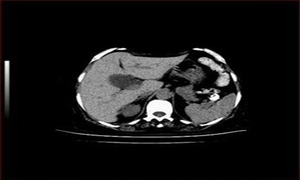

胆瘅,中医病名。是因湿热邪毒壅积于胆,胆汁及气血瘀滞而化热。以右上腹痛,呕吐,发热等为主要表现的内脏瘅(热)病类疾病。本病相当于西医学所说的急性胆囊炎。胆瘅常合并有胆石。少数病重者可伴胆囊穿孔,发为脂膜瘅(急性腹膜炎)等病。

5、X线腹部平片可见肿大的胆囊阴影,或见到结石阴影。B超检查可见胆囊壁增厚的毛草现象,或有结石反射波。